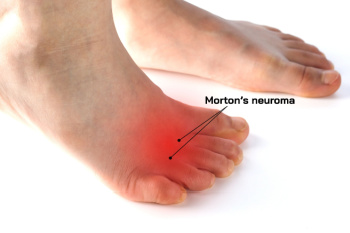

Morton's neuroma involves the thickening of a nerve in the foot, most often found between the third and fourth toes. It results from persistent pressure and irritation, which can lead to pain, numbness, or tingling in the toes and the ball of the foot. Symptoms of Morton’s neuroma include a burning sensation or the feeling of a small lump under the foot. Women are more commonly affected, likely due to wearing narrow, high-heeled shoes that force the bones of the feet into unnatural positions. Being overweight can also increase the risk. A podiatrist can diagnose Morton's neuroma by examining the foot and evaluating the pain’s location and severity. They can offer such treatment solutions as custom orthotics, changes in footwear, or in some cases, injections to reduce inflammation. If conservative approaches are not effective, surgery may be considered. If you have symptoms that may indicate Morton's neuroma, it is suggested that you schedule an appointment with a podiatrist.

Morton's neuroma is a painful foot condition that commonly affects the areas between the second and third or third and fourth toe, although other areas of the foot are also susceptible. Morton’s neuroma is caused by an inflamed nerve in the foot that is being squeezed and aggravated by surrounding bones.

Morton’s neuroma, (also referred to as Morton’s metatarsalgia, Morton’s neuralgia, plantar neuroma or intermetatarsal neuroma) is a condition that is caused when the tissue around one of the nerves between your toes begins to thicken. This thickening can result in pain in the ball of the foot. Fortunately, the condition itself is not cancerous.

Morton’s neuroma affects women more often than men with a ratio of 4:1. It tends to target women between the age of 50 and 60, but it can occur in people of all ages. There are some risk factors that may put you at a slightly higher risk of developing the condition. People who often wear narrow or high-heeled shoes are often found to be linked to Morton’s neuroma. Additionally, activities such as running or jogging can put an enormous amount of pressure on the ligament and cause the nerve to thicken.

There usually aren’t any outward symptoms of this condition. A person who has Morton’s neuroma may feel as if they are standing on a pebble in their shoe. They may also feel a tingling or numbness in the toes as well as a burning pain in the ball of their foot that may radiate to their toes.